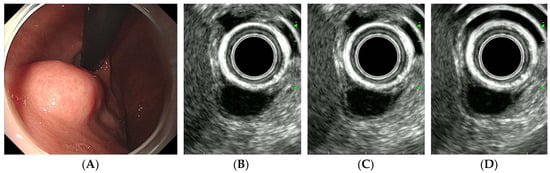

| CE-EUS findings | |||

| Arterial phase | |||

| Arterial enhancement | 0.024 | ||

| No/hypo-enhancement | 7 | 2 | |

| Iso/hyper-enhancement | 20 | 39 | |

| Irregular vessels | 0.017 | ||

| Absent | 21 | 20 | |

| Present | 6 | 21 | |

| Venous phase | |||

| Diffuse enhancement | 0.035 | ||

| Absent | 9 | 5 | |

| Present | 18 | 36 |